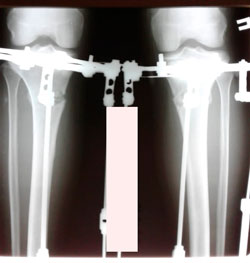

на фиксации